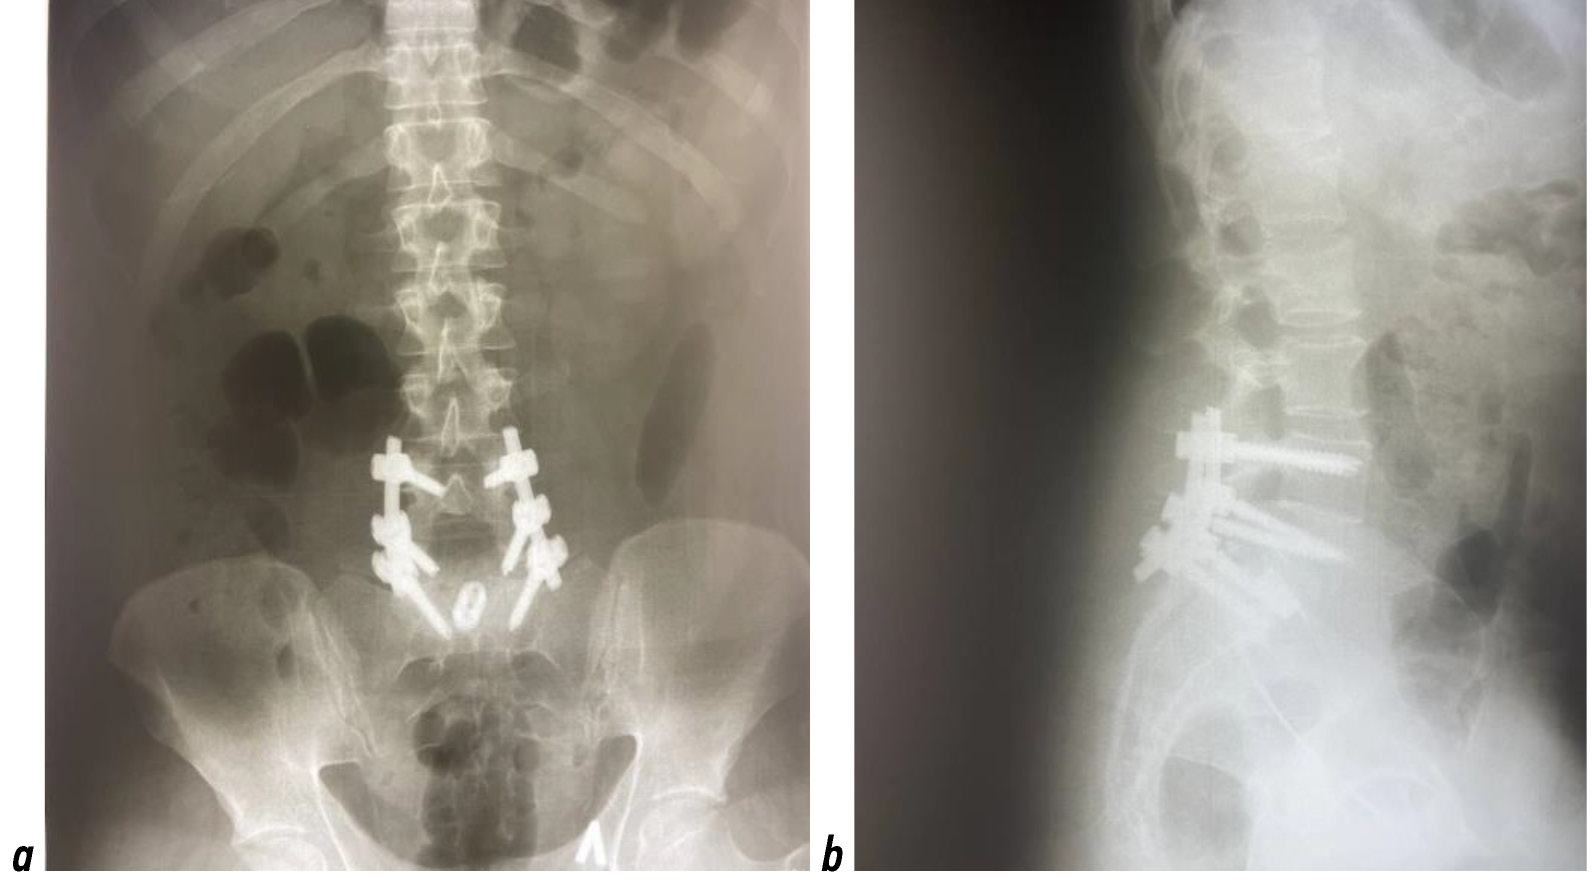

Пациентка Ф., 32 лет, обратилась в НМИЦ нейрохирургии им. акад. Н.Н. Бурденко для консультации в мае 2021 года. На момент обращения срок гестации составлял 31 неделю. Из анамнеза известно, что в 2013 году, катаясь на сноуборде, пациентка упала на область ягодиц, после чего появились постоянные боли в пояснице. При обследовании по данным МРТ были выявлены МР-признаки переднего спондилолистеза III степени в сегменте L5–S1 со спондилолизом позвонка L5. Получала консервативную терапию с временным положительным эффектом. Со временем боль в пояснице усилилась, стала иррадиировать в левую нижнюю конечность, что послужило причиной обращения и проведения через 2 года после травмы обследования в НМИЦ травматологии и ортопедии им. Н.Н. Приорова. При обследовании в 2015 году по данным рентгенографии диагностирован спондилолизный спондилолистез L5 позвонка (рис. 1).

Рис. 1. Рентгенограмма пояснично-крестцового отдела позвоночника пациентки Ф. до операции: а ― фронтальная проекция; b ― сагиттальная проекция. Спондилолизный спондилолистез L5 позвонка указан стрелкой.

Fig. 1. X-ray of the lumbosacral spine of patient F. before neurosurgical operation: а ― frontalis projection; b ― sagittalis projection. Spondylolysis spondylolisthesis of the L5 vertebra is indicated by an arrow.